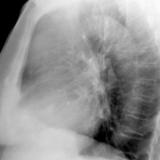

Case 8b Thymoma Lat

Date: 03/27/2009

Views: 14096